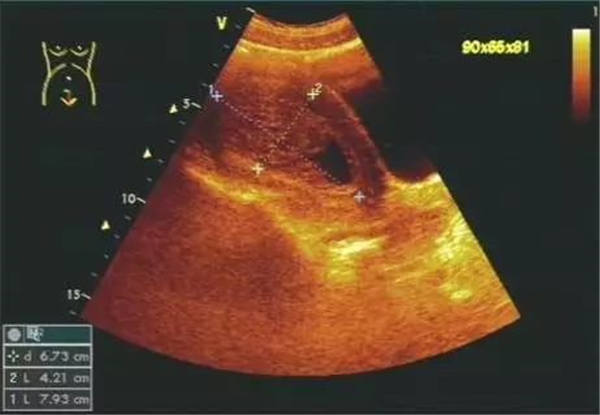

2、宫腔积血、积脓、积液

(宫腔积液)